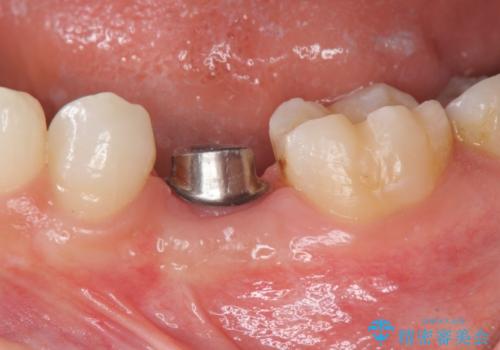

- 大人になっても残存していた乳歯がグラグラし、痛くて噛めない 抜いて欲しいとの希望で来院されました。

歯根が吸収し残すことのできない乳歯を抜去後、隣の歯を削らずに済むインプラント治療で咬合機能の回復を計画します。

乳歯の抜去後、インプラントを用いてしっかりと咬合機能を回復することができました。